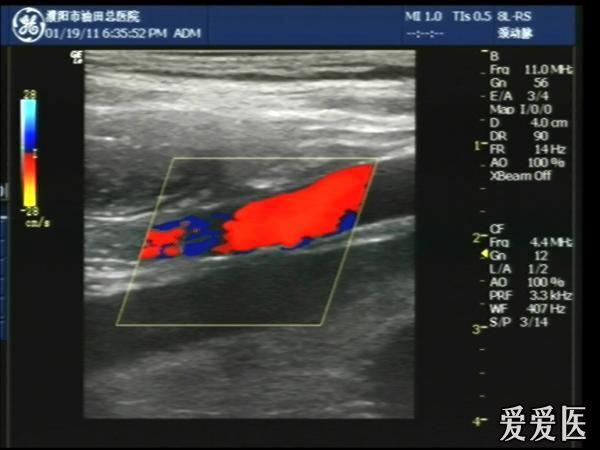

超声检查:于下腹部可见“双环征象”,双环重叠长约6mm,检查期间观察可见肠蠕动;CDFI:未见明显异常血流信号。

超声提示:下腹部双环征,考虑肠套叠可能,请结合临床